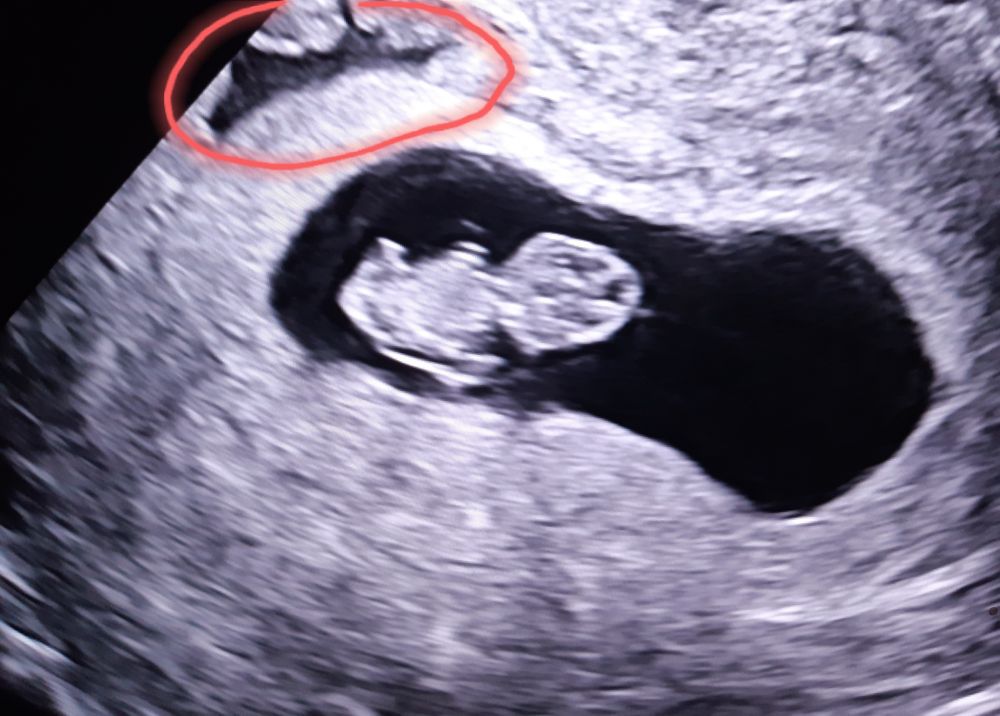

В жк и стационаре тоже писали ретрохориальная гематома , тоже увеличилась за неделю , но ре опроверг , сказал плацента подрастет и эту кровяную жидкость расплющит, это физиологический процесс, а гематома это сгусток его у меня нет , думаю у Вас тоже самое, не волнуйтесь. Выделений не было .

Виолетта, о! Спасибо за фото. А то везде гематома выглядит не такой черной.

Сальма♥МЕБЕЛЬ♥Орматек♥38Попуг, гематома в кавычках, ре сказал это не гематома )) в жк писали 1×0,6 , через неделю с сильным токсикозом легла в стационар 3×0,6 через4 дня при выписке 2,3×0,4 , как сказал ре это жидкость она не будет постоянной формы и размера , и через 2 -3 недели когда плацента поднимется её вообще не видно будет